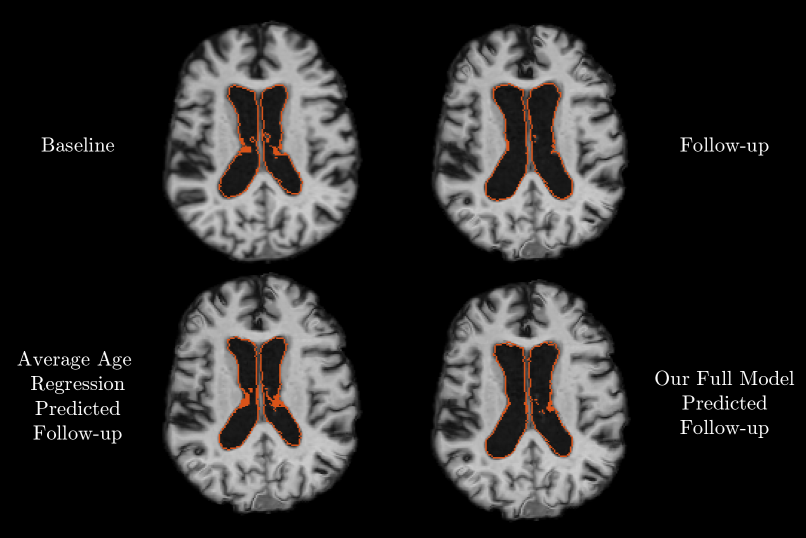

4.2 Anatomical Prediction

We also evaluate the model for full anatomical scan prediction. An example prediction is shown in Fig. 4. To quantify prediction accuracy, we propagate segmentation labels of relevant anatomical structures from the baseline scan to the predicted scan using the predicted warps. We compare the predicted segmentation label maps with the actual segmentations of the follow-up scans. The warps computed based on the actual follow-up scans through the atlas provide an indication of the best accuracy the predictive model could achieve when using warps to represent images. Similar to the volumetric predictions, the full model offers modest improvements when evaluated on the entire test set, and substantial improvements in segmentation accuracy when evaluated in the subjects who exhibit large volume changes between the baseline scan and the follow-up scan, as reported in Fig. 5 and exemplified in Fig. 6. In both experiments, all components and contributed significantly to the improved predictions.

4.3 Example Application

To demonstrate the potential of the anatomical prediction, we predict the follow-up scan of a patient diagnosed with dementia as if the patient were healthy. Specifically, we train our model using healthy subjects, and predict follow-up scans for AD patients. In Fig. 7 we illustrate an example result, comparing the areas of brain anatomy that differ from the observed follow-up in the predicted healthy brain of this AD patient. Our prediction indicates that ventricle expansion would be different if this patient had a healthy trajectory.